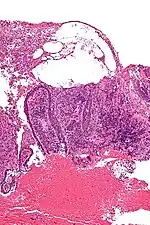

Micrograph of pemphigus vulgaris with the characteristic "tombstoning". H&E stain.

Pemphigus is an autoimmune disease caused by antibodies directed against both desmoglein 1 and desmoglein 3 present in desmosomes. Loss of desmosomes results in loss of cohesion between keratinocytes in the epidermis, and a disruption of the barrier function served by intact skin. The process is classified as a type II hypersensitivity reaction (in which antibodies bind to antigens on the body's own tissues). On histology, the basal keratinocytes are usually still attached to the basement membrane leading to a characteristic appearance called "tombstoning". Transudative fluid accumulates in between the keratinocytes and the basal layer (suprabasal split), forming a blister and resulting in what is known as a positive Nikolsky's sign. This is a contrasting feature from bullous pemphigoid, which is thought to be due to anti-hemidesmosome antibodies, and where the detachment occurs between the epidermis and dermis (subepidermal bullae). Clinically, pemphigus vulgaris is characterized by extensive flaccid blisters and mucocutaneous erosions. The severity of the disease, as well as the mucosal lesions, is believed to be directly proportional to the levels of desmoglein 3. Milder forms of pemphigus (like foliacious and erythematoses) are more anti-desmoglein 1 heavy.